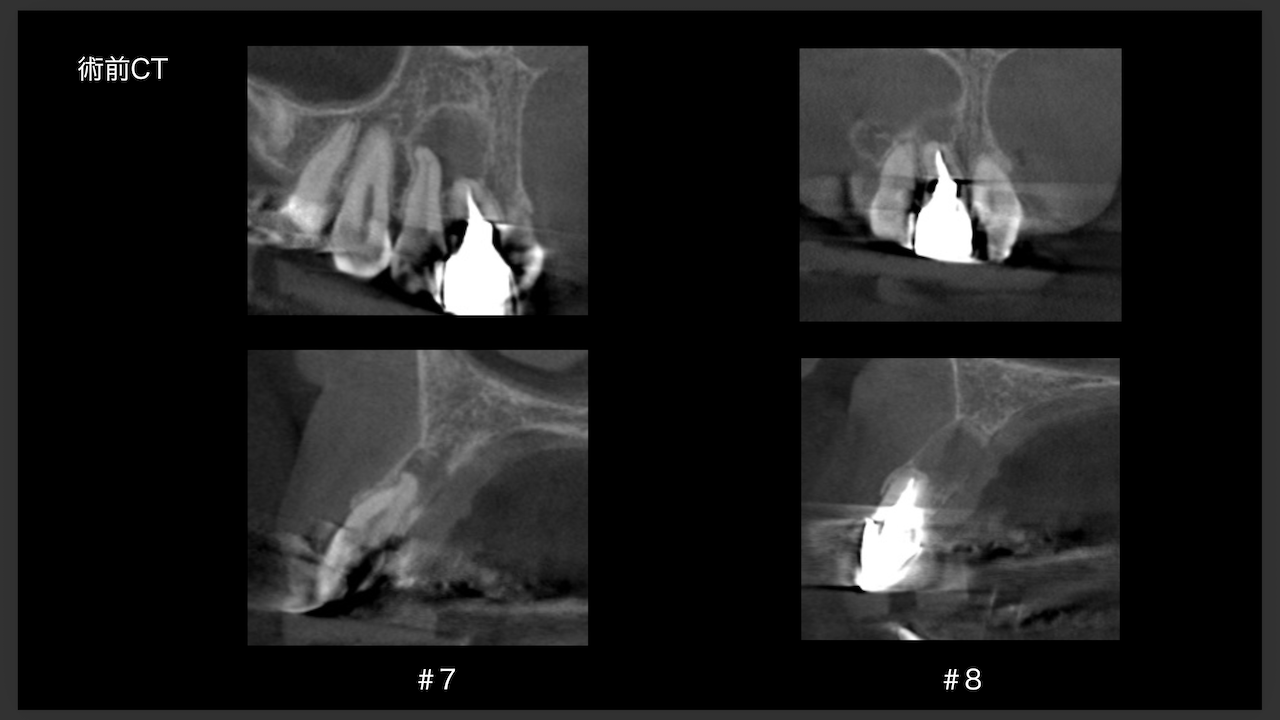

CBCTでは2本とも口蓋側の皮質骨が消失している。

という絶望的な状況である。

が、

術前にその予後を患者さんに説明し、

治療へ移行した。